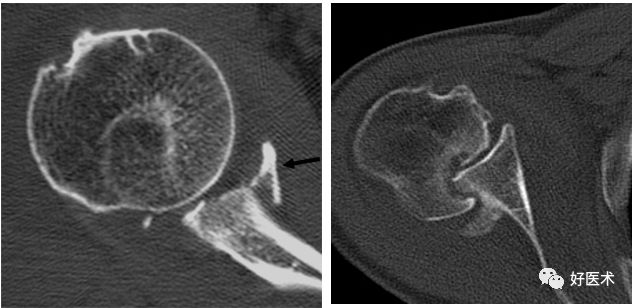

五、CT检查

能很好地观察关节的稳定性、骨皮质连续性,可以观察不易发现的关节内骨片

-

准确评估骨性Bankart病变、Hill-sachs病变

CT显示肩关节不稳

后脱位:反Hill-Sachs损伤

后关节盂撕脱小骨折

若盂唇损伤合并关节盂骨质损伤,称为骨性Bankart病变

骨性Bankart病变